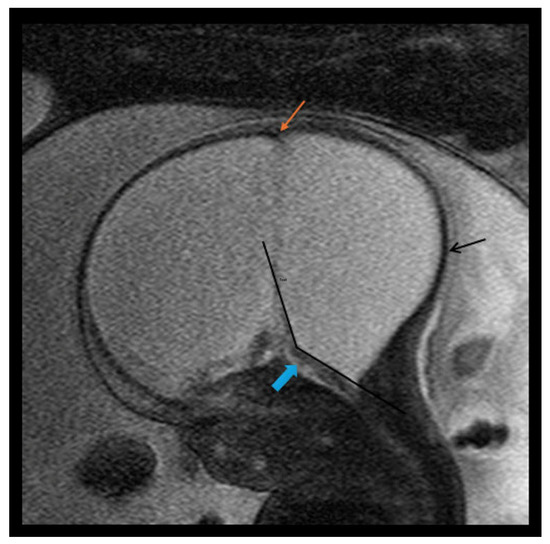

| TVA (°) * | 93.7° ± 18.1° (n = 6) | 50.9° ± 17.3° | 21.7° (SD, 15.5°) | <0.001 |

| Enlarged CM * | 7/7 (100%) | 7/14 (50%) | 3/6 (50%) | 0.002 |